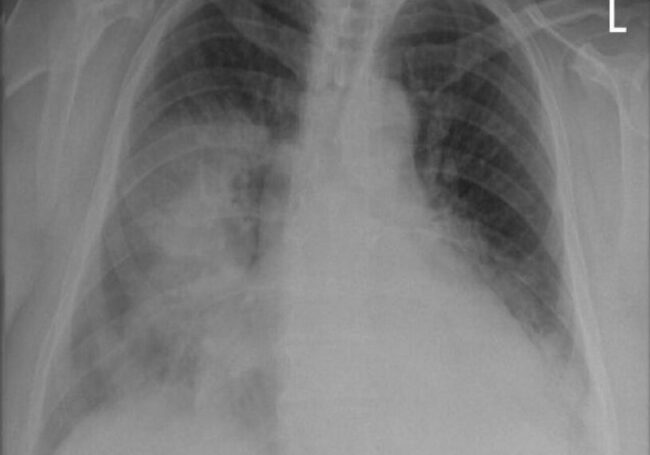

Researchers have developed a deep learning model that can predict a person’s 10-year risk of death from a stroke or heart attack. It can factor that information from a single chest X-ray (CXR). The model is an advanced type of artificial intelligence (AI) that is trained to detect patterns associated with the disease through X-ray images.

The model known as CXR-CVD risk was developed by Dr. Weiss and a team of researchers. Together they trained a deep learning model using a single CXR as input. Researchers created the model to foresee the risk of death from cardiovascular disease. They used 147,497 chest X-rays from 40,643 participants in the Prostate, Lung, Colorectal, and Ovarian Cancer Screening Trial. The trial is a multi-center, randomized controlled trial designed. The whole thing was sponsored by the National Cancer Institute.

The model’s usage of an X-ray is a unique approach. X-rays are “acquired millions of times a day across the world,” Dr. Weiss said. “Based on a single existing [CXR] image, our [CXR-CVD risk] model predicts future major adverse cardiovascular events with similar performance and incremental value to the established clinical standard.”